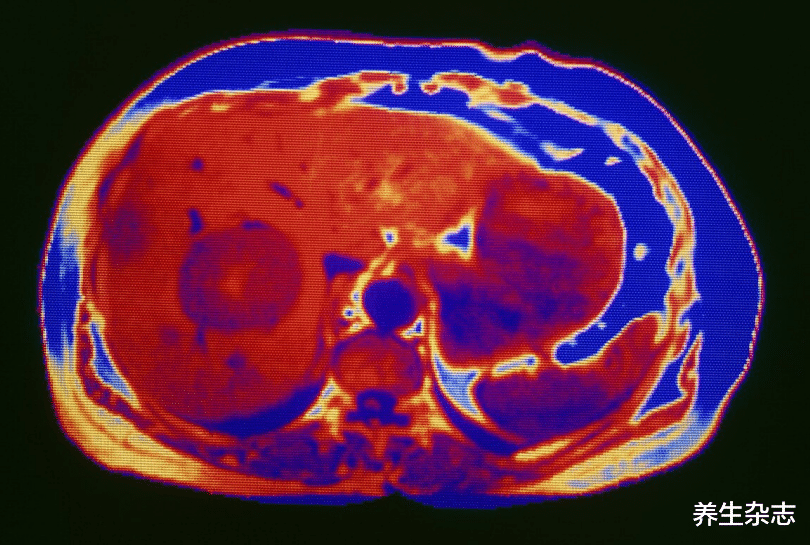

身体常摄入此类物质 , 会引起肝脏组织的衰竭 , 从而损伤肝细胞 , 进而引起肝硬化和肝炎 , 甚至引发肝癌 。